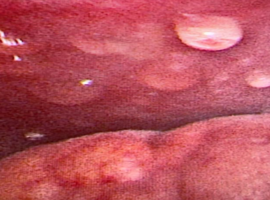

Identification of a PKD1 Non-truncating Variant Presenting with a Rapid Progression: A Case Report